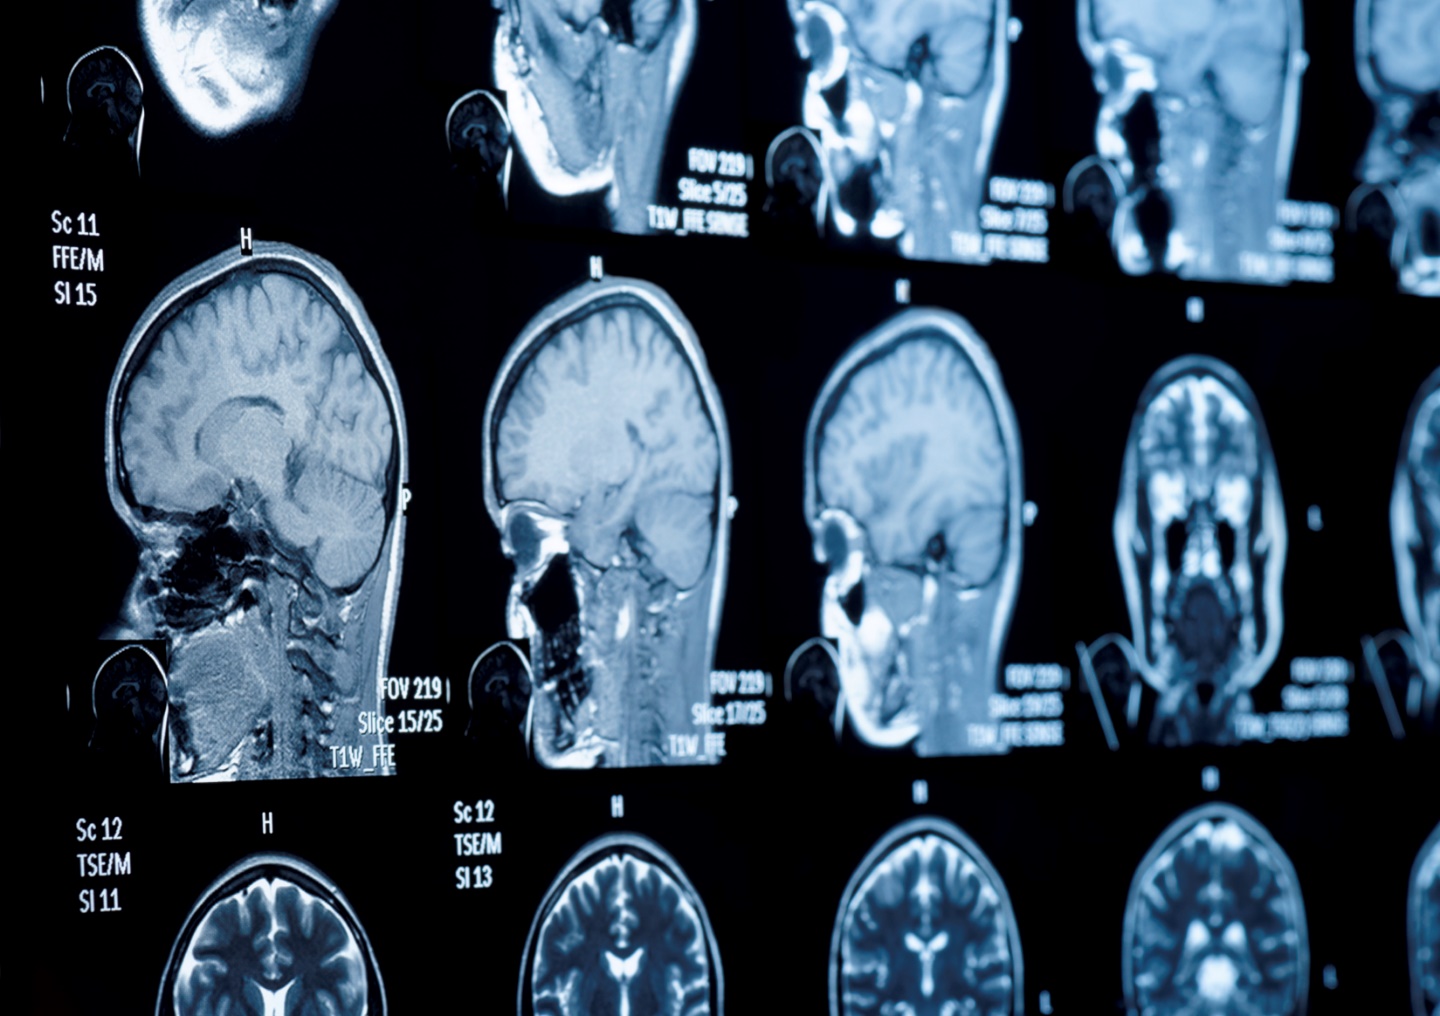

Un recente studio internazionale, guidato dal Mass General Brigham negli Stati Uniti, ha identificato un circuito cerebrale specifico responsabile della creatività umana. Questo circuito sarebbe regolato dalla regione frontale dell’emisfero destro e la sua attività può essere influenzata da lesioni cerebrali e malattie neurodegenerative.

Come riportato da Elisa Buson su Ansa.it, la ricerca pubblicata sulla rivista JAMA Network Open, ha analizzato i dati di oltre 800 individui e 36 studi di risonanza magnetica funzionale. I risultati hanno mostrato che diverse regioni cerebrali sono coinvolte nelle attività creative, formando un circuito interconnesso. Questo circuito fa capo al polo frontale destro, un’area cruciale per il controllo cognitivo e l’autocensura.